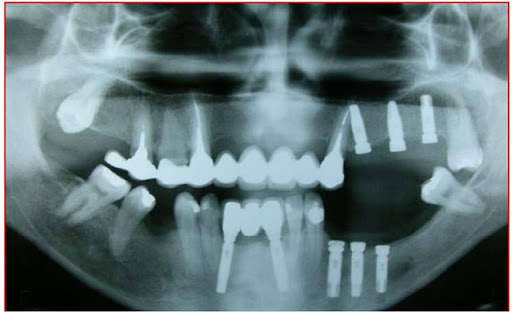

No pós-operatório são prescritas as orientações com o ferimento cirúrgico, antibioticoterapia, antiinflamatórios e analgésicos. São avaliadas periodicamente as alterações sensoriais e sua evolução, além dos controles radiográficos dos implantes (Fig. 14).

Fig. 14 - Controle radiográfico ortopantomográfico dos implantes e da alteração na anatomia mandibular.

O tempo de carga dos implantes normalmente é postergado para 6 a 8 meses após a fixação dos implantes (10), devido à remoção de estrutura óssea na região entre as corticais superior e basal (Figs. 15, 16 e 17).

Os implantes fixados juntamente com a transposição do NAI apresentam taxa de sucesso semelhante aos implantes fixados sem auxílio de outras técnicas e, excetuando as alterações sensoriais, as complicações relatadas na literatura também são comuns àquelas presentes nas fixações de implantes sem uso de técnicas avançadas.